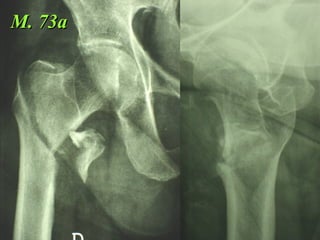

M. 73a

La placca a compressione percutanea (PC.C.P.) di Gotfried è un mezzo di sintesi studiato per assicurare un “impattamento controllato” delle fratture pertrocanteriche grazie alle due viti telescopiche prossimali che garantiscono una ottima stabilità rotazionale

Tradizionalmente si ritiene importante per la stabilità delle fratture pertrocanteriche l’integrità della parte mediale della metafisi prossimale del femore

In realtà la zona più importante per la ricostruzione di questo tipo di fratture è il muro laterale contro il quale si impatta il frammento metaepifisario mediale

Se il muro laterale è rotto o viene lesionato durante la sintesi , come spesso accade in fase di applicazione della vite cefalica dei chiodi endomidollari o della vite-placca, andremo incontro al collasso della frattura e ad un conseguente lungo periodo di impotenza funzionale

Con la placca di Gotfried non si è mai riscontrato un danno iatrogeno del muro laterale e nessun collasso della frattura.Ciò è dovuto al fatto che i fori per l’applicazione delle due viti prossimali sono di piccolo diametro (9 mm) rispetto ai 16-32 mm necessari per introdurre la vite cefalica di un chiodo endomidollare o di una vite-placca a compressione.

Dal Gennaio 2005 ad Agosto 2006 110  placche di Gotfried Età media  : 78 anni (range 29-94) Tempo chirurgico: 30 minuti (range 12-45) IMMEDIATA CONCESSIONE DEL CARICO